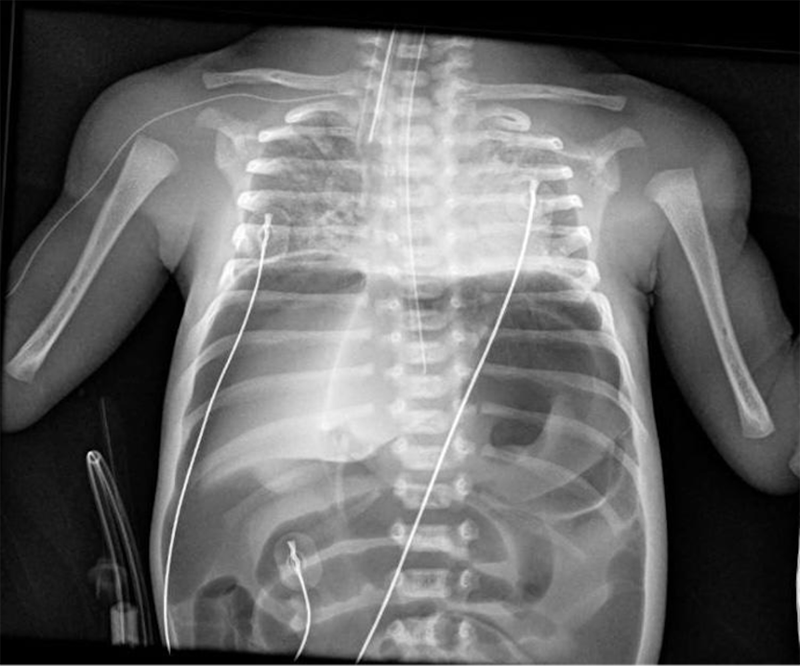

I­nes­ta­bi­li­dad y dis­ten­sión ab­do­mi­nal sú­bi­ta en un pre­ma­tu­ro de 32 se­ma­nas

Varón de 32 semanas de gestación, segundo gemelar, de 1850 g, nacido mediante cesárea urgente por amniorrexis prolongada, muerte del primer gemelo, leucocitosis y fiebre materna. Apgar 6/8. Precisa CPAP nasal las primeras horas de vida con buena evolución.